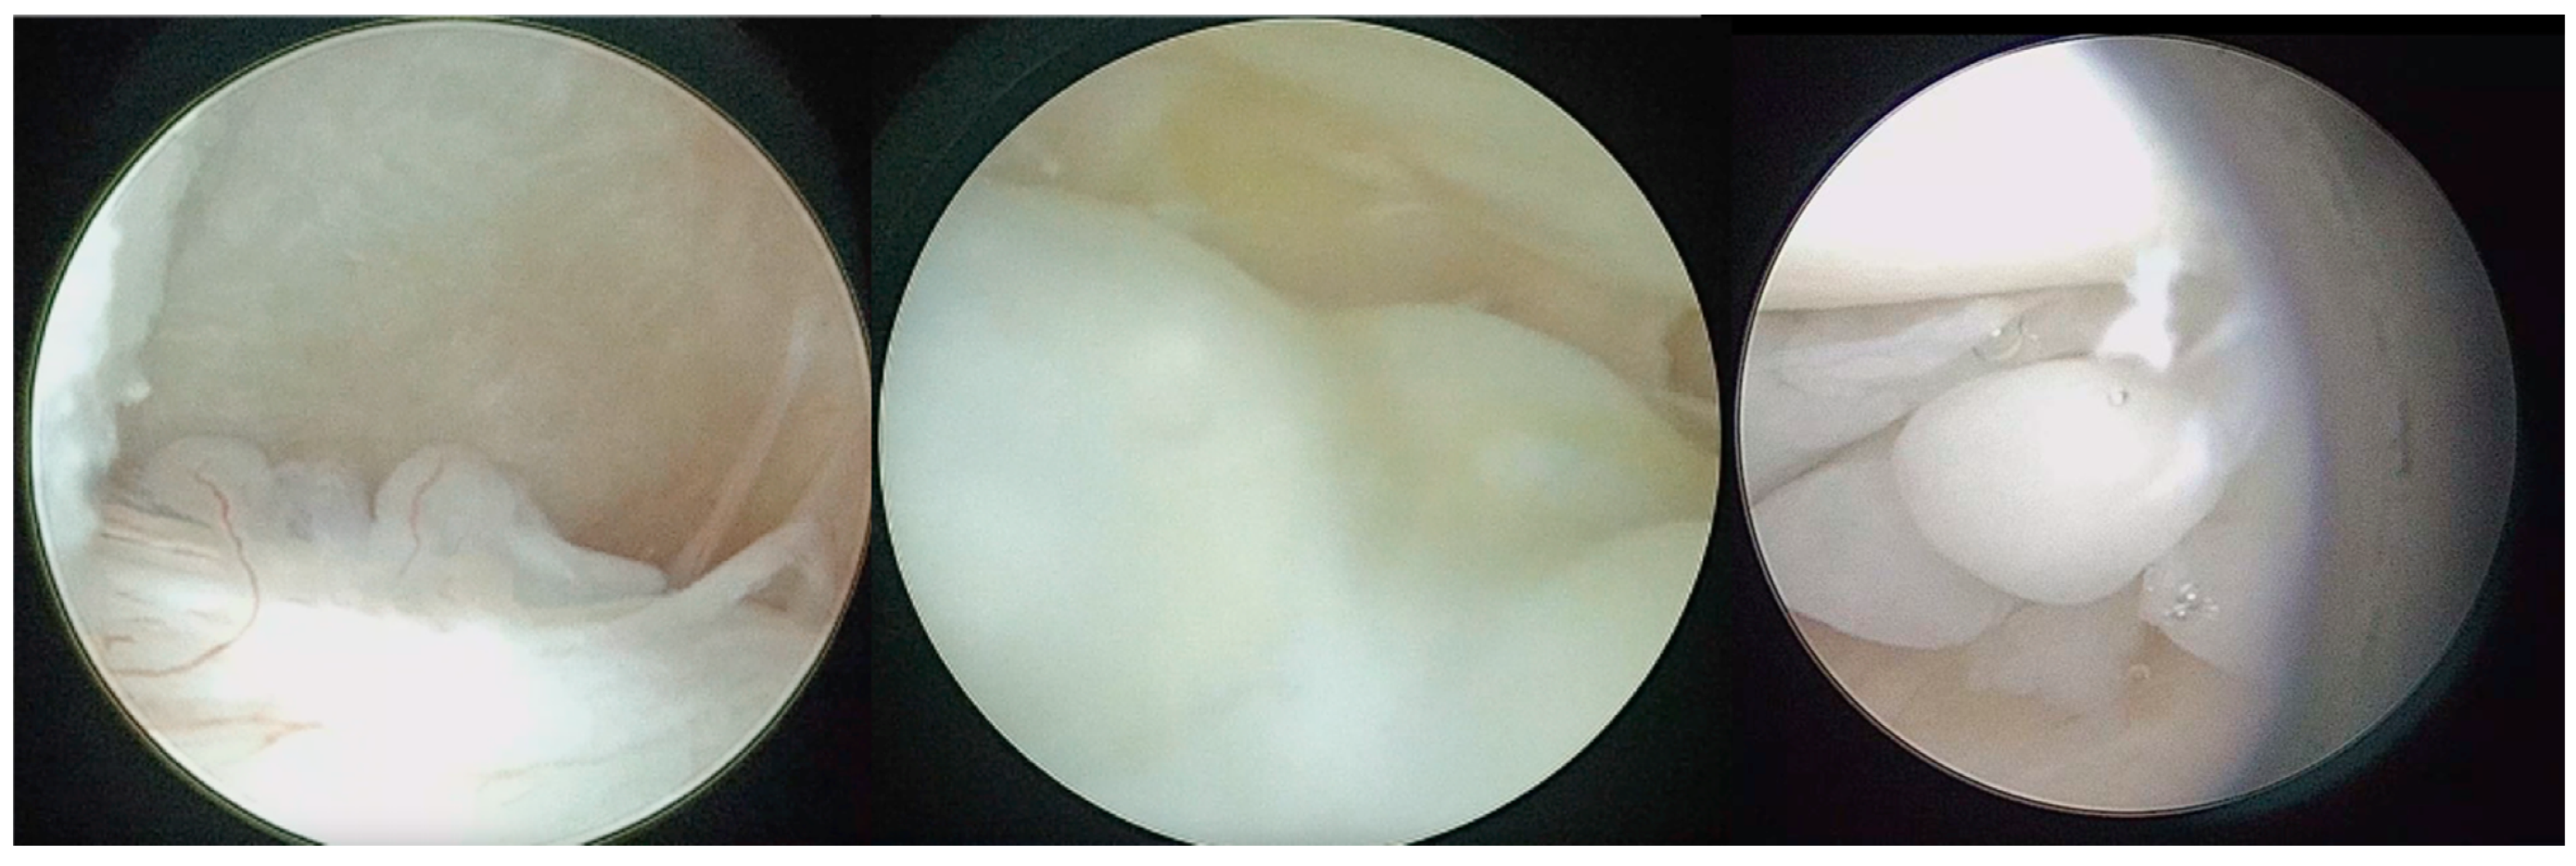

Figure 3.

Polyps with vascular axial supply, subsynovial nodules, and LBs.

Figure 4.

Triangulation technique and LBs washout from the second cannula, which can be seen lying on the patient’s face.